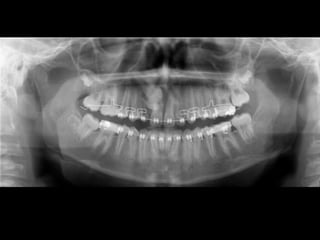

RADIOGRAFÍAS PANORÁMICAS